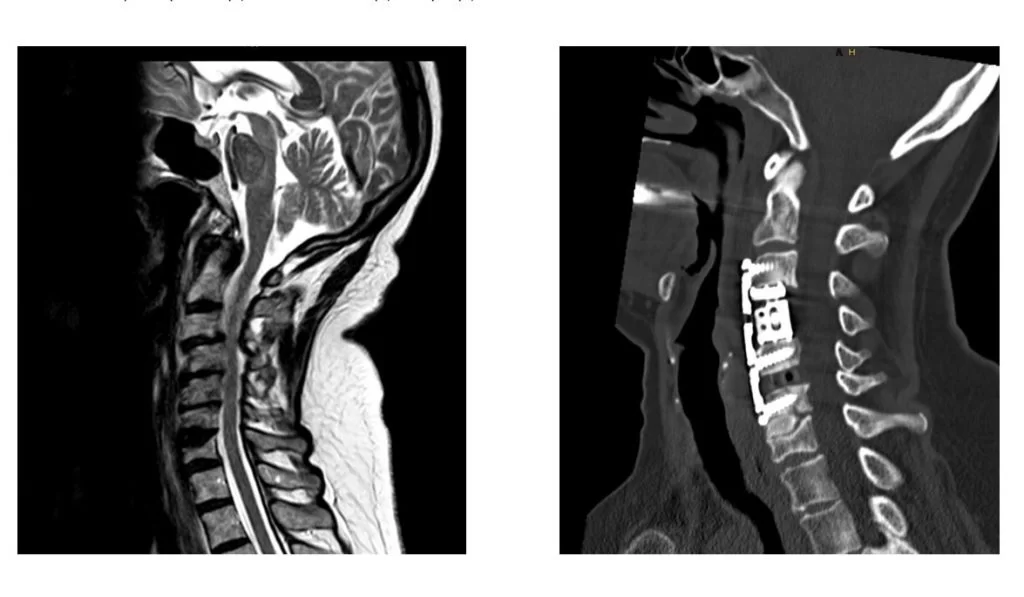

- Στένωση του σπονδυλικού σωλήνα στον αυχένα: Συνήθως η στένωση του σπονδυλικού σωλήνα στον αυχένα αντιμετωπίζεται με δισκεκτομή ή πεταλεκτομή. Σε μερικές περιπτώσεις όμως, όταν π.χ. η πίεση είναι πρόσθια και εκτείνεται σε όλο το μήκος του σπονδυλικού σώματος, ενδέχεται να χρειαστεί σωματεκτομή (Εικόνα 1).